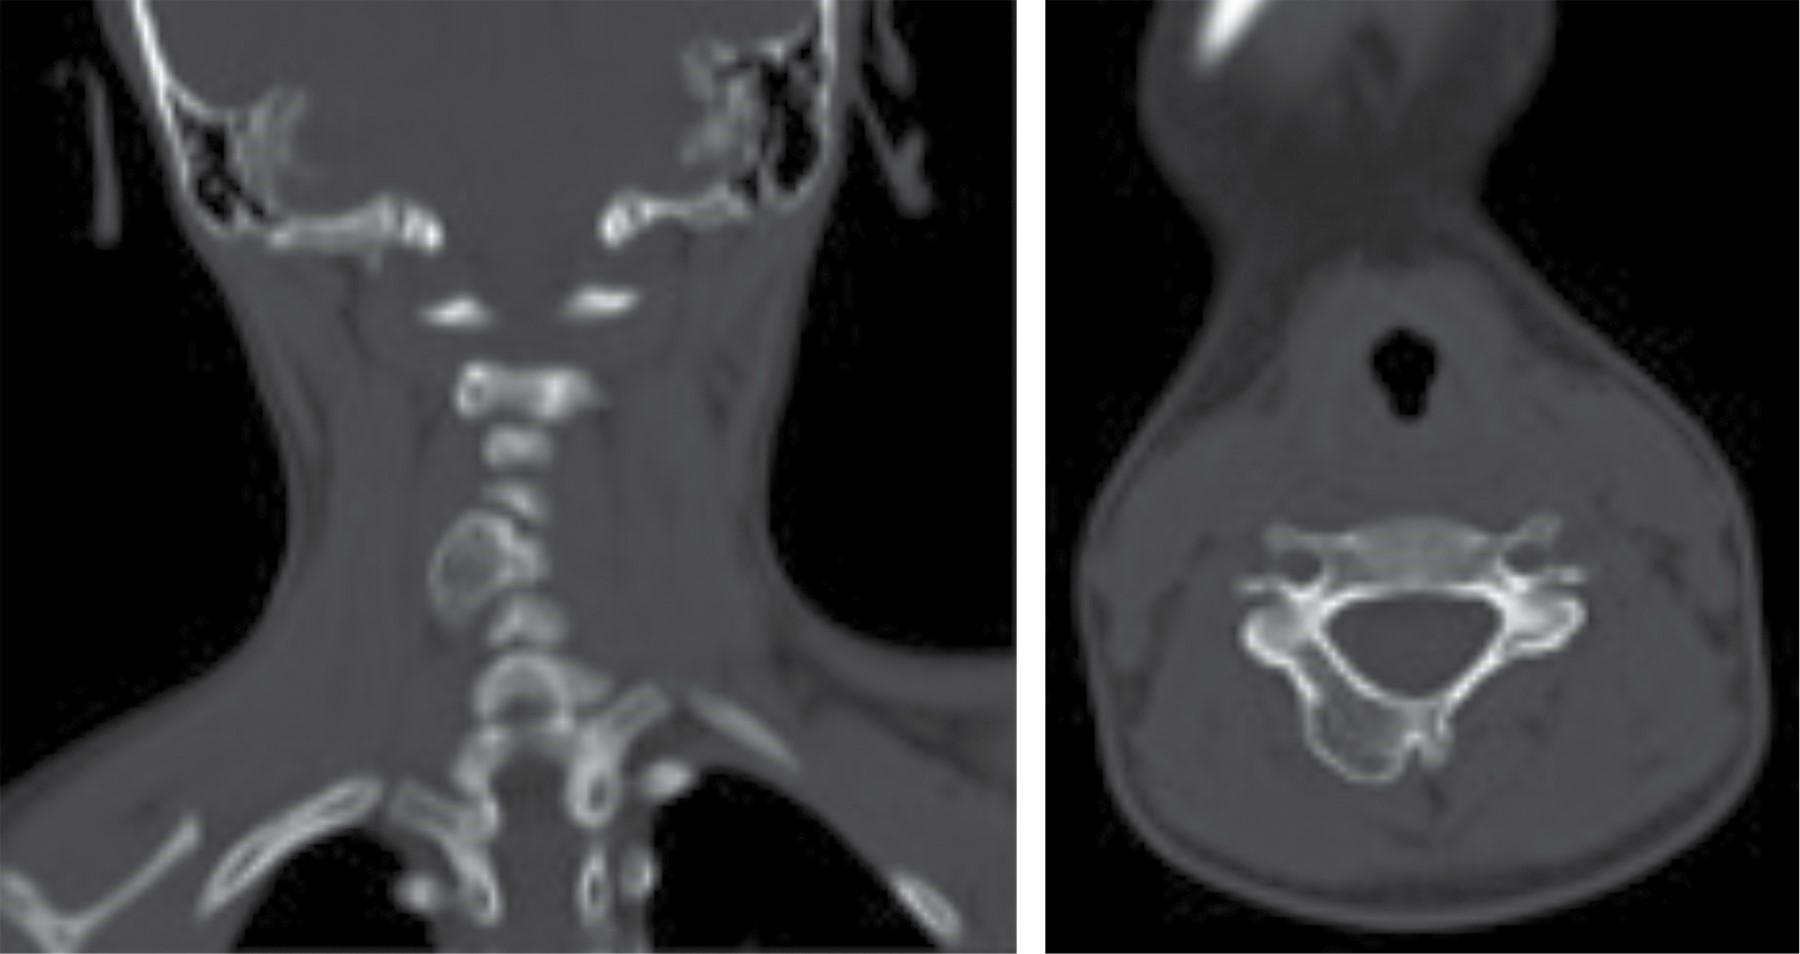

Se solicitan estudios de analítica sanguínea, en los que se encuentra fosfatasa alcalina de 312 unidades/litro que se considera normal por actividad ósea fisiológica; ultrasonografía con reporte de lesión sólida de componente óseo paracervical derecho, probable osteocondroma; tomografía axial computarizada simple donde se aprecia imagen hiperdensa en lámina derecha de quinto cuerpo vertebral, única, de aproximadamente 15 × 20 mm (Figura 3); resonancia magnética nuclear simple que reporta imagen hiperintensa que rebasa bordes, de aproximadamente 15 × 20 mm, en lámina derecha de quinto cuerpo vertebral (Figura 4) y gammagrafía ósea con MDP que indica actividad osteoblástica con discreto aumento en quinto cuerpo vertebral cervical principalmente lado derecho, no se observan zonas de infiltración ósea.

Figura 3